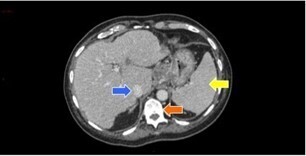

Question 3 - Dans les coupes précédentes, quelles sont les structures désignées par les flèches ?

Veine cave inférieure.

Corps vertébral.

Voies veineuses de dérivation péri-gastriques.

Question 4 - Vous constatez (une ou plusieurs réponses exactes) :

Non pas du foie gauche (= lobe gauche + segment IV) mais du lobe gauche (segments II et III).

Flèche verte.

La dysmorphie hépatique est caractérisée par une hypertrophie de segment I (en arrière du tronc porte et en avant de la veine cave inférieure) et du lobe gauche (segments II et III situés à gauche de la veine hépatique gauche) ; ainsi que par une hypotrophie du segment IV (situé entre les veines hépatiques gauche et médiane, séparé du lobe gauche par le plan passant par la veine hépatique gauche et le ligament rond). Peut également s’y associer une hypotrophie du secteur postérieur du lobe droit (segments VI et VII).

Pour la segmentation hépatique, voir la figure ci-dessous : On retrouve comme autre signe d’hépatopathie chronique les contours bosselés.

Les signes d’hypertension portale visibles en scanner sont :

– les voies veineuses de dérivation porto-systémiques (spléno-rénales, gastro-rénales, mésentériques, rétro-péritonéales…) ;

– la splénomégalie.